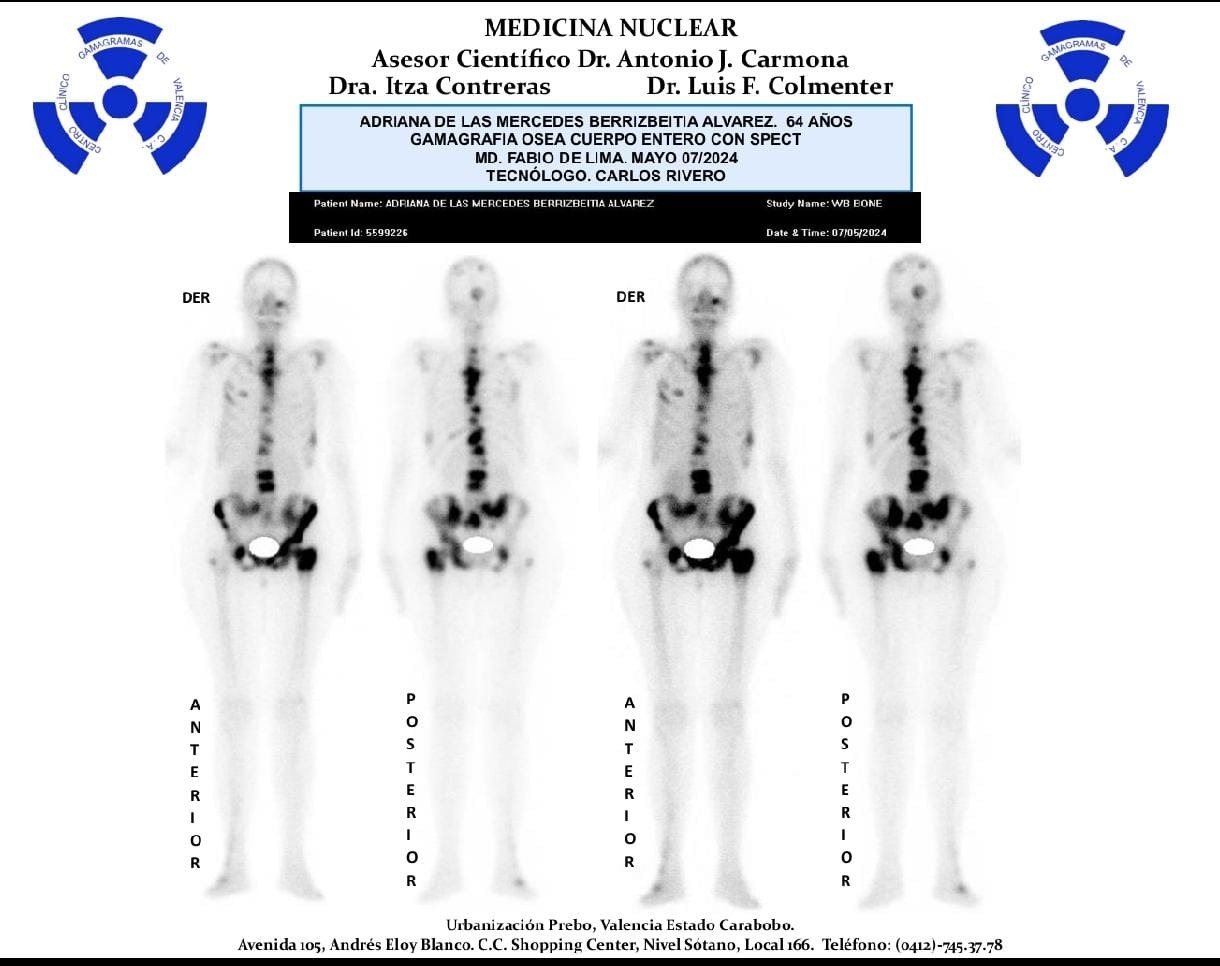

Five years ago, she was diagnosed with triple-negative breast carcinoma and has been fighting tirelessly ever since. She underwent chemotherapy, radiotherapy, and had a radical mastectomy with lymph node dissection. Currently, she has been diagnosed with bone metastasis and lung lesions, which require urgent and specialized medical care.

To continue her treatment, she must undergo several costly medical procedures, including CT scans, bone scans, MRIs, ultrasounds, and lab tests. In addition, she will receive chemotherapy and possibly radiotherapy once again.

Hace cinco años fue diagnosticada con un carcinoma mamario triple negativo y, desde entonces, ha luchado incansablemente. Recibio tratamientos de quimioterapia, radioterapia y se realizó una mastectomía radical con vaciamiento ganglionar. Actualmente, su diagnóstico es de metástasis ósea y lesiones en los pulmones, lo que requiere atención médica urgente y especializada.

Para continuar su tratamiento, necesita realizarse una serie de estudios médicos costosos, como tomografías, gammagramas óseos, resonancias magnéticas, ecografías y análisis de laboratorio. Además, recibirá quimioterapia y posiblemente radioterapia nuevamente.